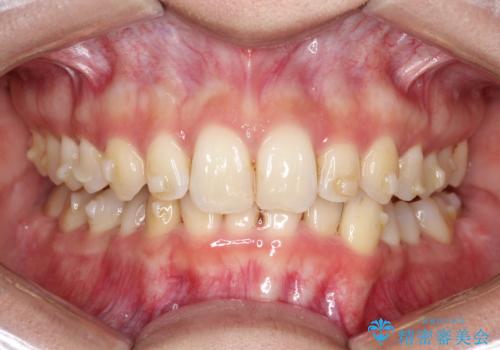

ディープバイト改善のためのインビザライン治療

- 患者様は、全体的な歯列のガタガタとディープバイト(深い噛み合わせ)を主訴として来院されました。診断の結果、ディープバイトを改善するためには、歯列全体の拡大が必要であると判断しました。治療には、透明なマウスピース型矯正装置「インビザライン」を使用し、歯を適切に拡大しながら歯並びを整える計画を立てました。治療期間はおおよそ2年を見込んで進め、最終的に見た目にも大きく変化をもたらすことを目指しました。

ディープバイトの治療には、奥歯の高さや前歯の位置に対する繊細な調整が必要です。本症例では、インビザラインによる歯列拡大を行うことで、噛み合わせを改善し、歯並び全体を整えました。治療過程では、歯間のスペースを確保するため、IPR(インタープロキシマルリダクション)を適宜行い、無理なく歯列の調整を行いました。治療後は、歯並びが大きく改善され、患者様の見た目にも大きな変化が現れました。インビザラインは透明で目立たず、治療中の見た目を気にされる患者様にも配慮した治療法です。